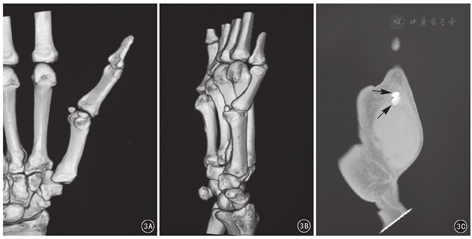

所有患者常规拍摄拇指正、侧位X线片。侧位X线片可见拇指掌指关节过伸,桡、尺侧籽骨均向远端移位,但桡侧移位程度更大,且桡侧籽骨与掌骨头关节面出现不匹配(图2)。术前均行CT检查。CT三维重建显示尺侧籽骨和掌骨头之间有正常的关节间隙,而桡侧籽骨骑坐于掌骨头上,二者之间的关节间隙消失;CT矢状位重建显示桡侧籽骨掌骨关节间隙消失,并可见桡侧籽骨除近侧缘外均由软组织包绕(图3)。